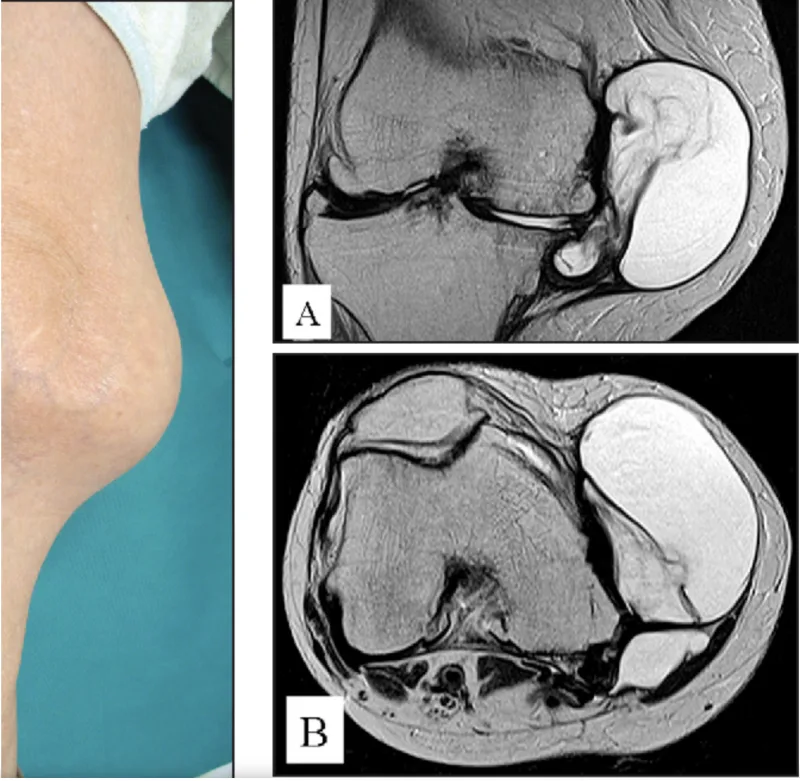

午前中, 先輩医師の整形外科クリニックから膝の内側に腫瘤がある中高年の患者さんが紹介されて受診.

膝関節の痛みを伴っており, 膝関節の内側後方寄りに5 cm大の腫瘤を認めました.

膝関節の内側が隆起しています.

MRI T2強調画像では, 白く写る液体を貯めた病変が内側半月板の内側に認められます.

引用元:Ohishi T. Arthroscopic decompression for a giant meniscal cyst. Orthopedics. 2016. 39.

腫瘤は, 囊腫(水が貯まった袋)状で, 膝関節の内側にある半月板後方から膝の内側に連続性に隆起しており, 半月板囊腫と診断.

変形性関節症も合併しており, 腫瘍ではないことから, 紹介元のクリニックで変形性膝関節症に対する治療を行っていただく様に返事を書きました.

半月板囊腫は, 傷ついた半月板から関節の外側に漏れ出た関節液が溜まった袋状の病変です.

多くは, 外側の半月板に生じますが, 内側に生じることも.

通常, 数 cmくらいですが, 時には大きくなり, 腫瘍を疑われることもあります.

痛みを伴うことがあり, 手術が必要となることもあります.